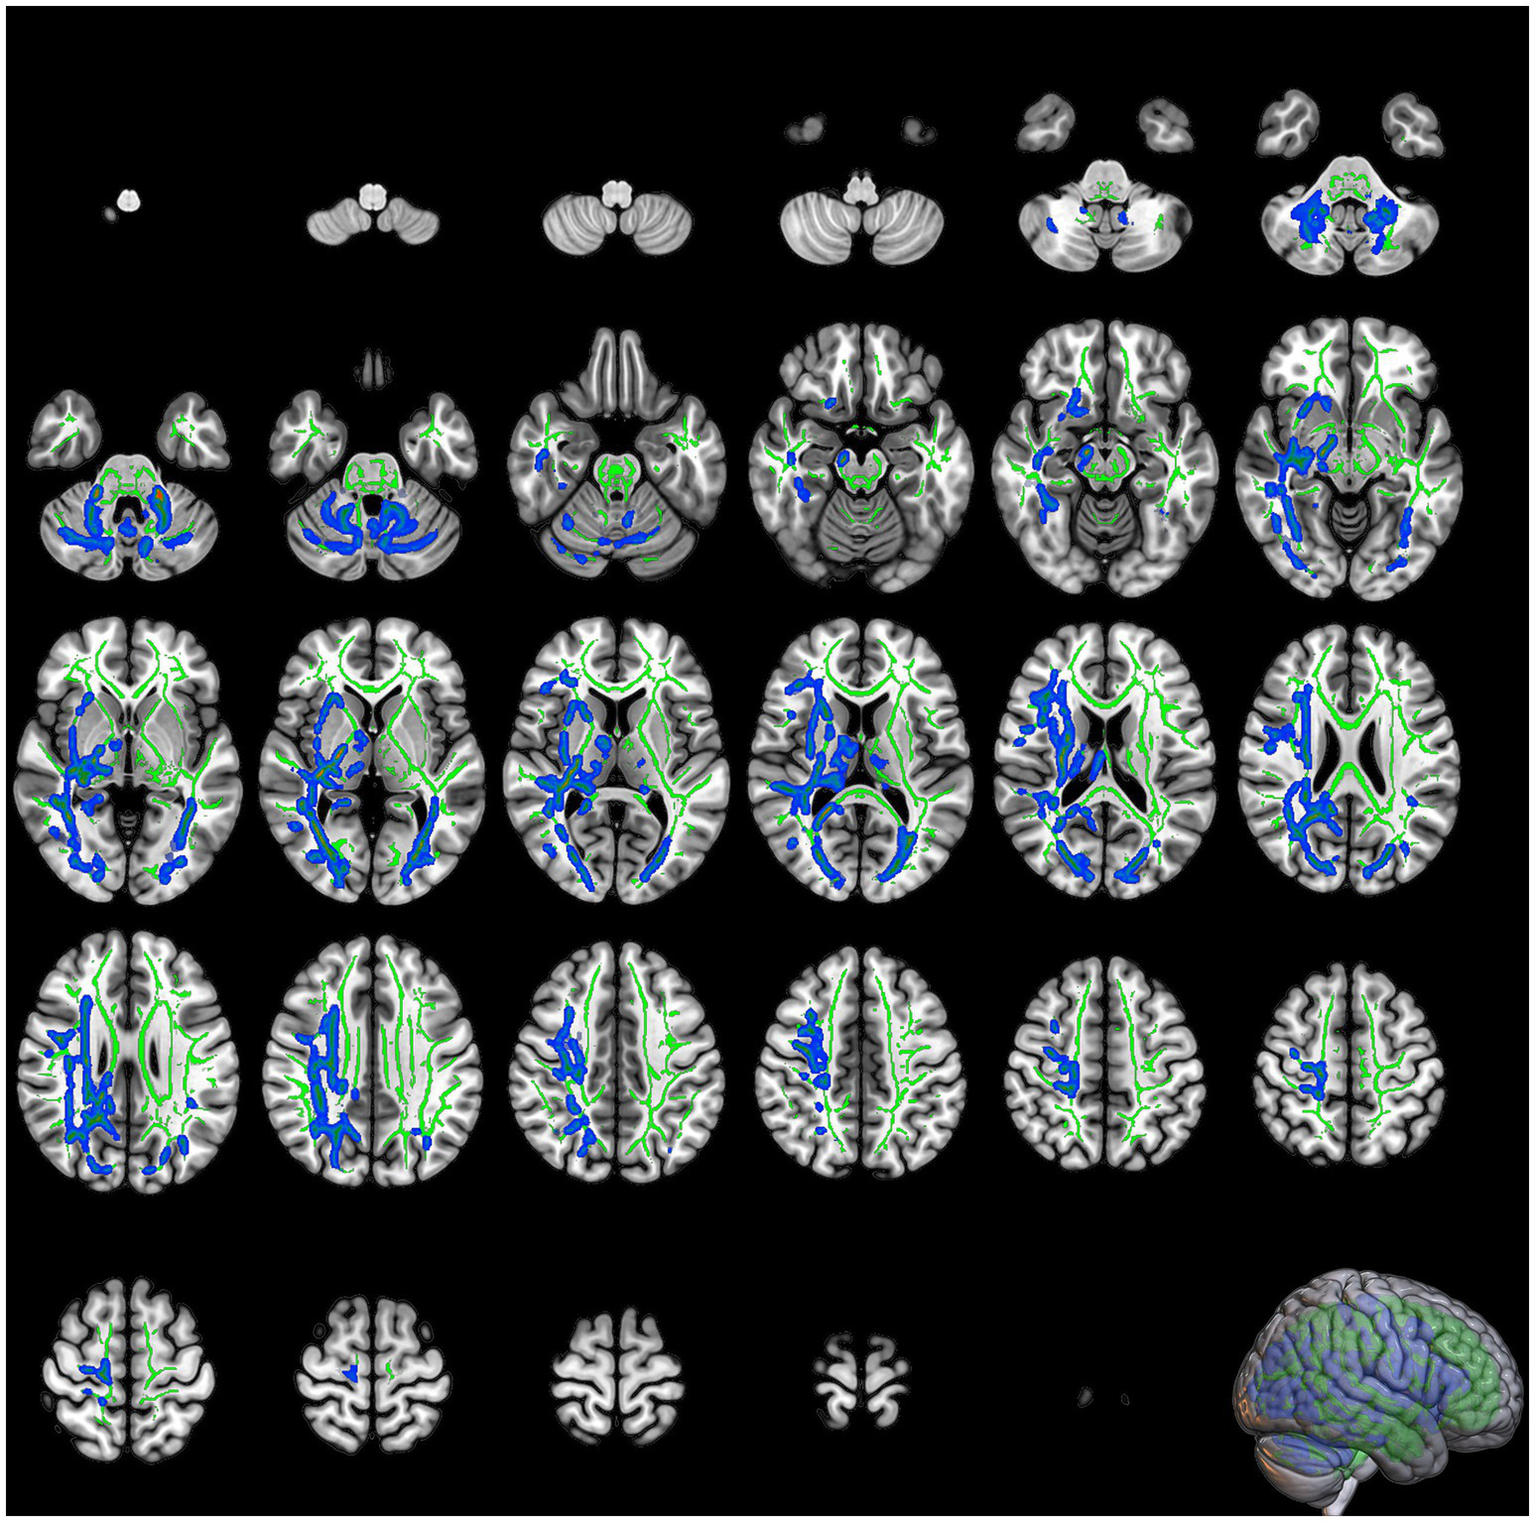

DKI analysis revealed that patients diagnosed with COVID-19 exhibited significant reductions in MK within the right IFOF, bilateral corticospinal tract, left IFOF, left inferior and superior longitudinal fasciculus (SLF), and left anterior thalamic radiation (Table 1; Figure 2). The most significant reduction in MK was observed in the right IFOF (cluster size: 14793 voxels, p = 0.02), followed by the left corticospinal tract (cluster size: 1964 voxels, p = 0.041).

Figure 2

The slices of significant clusters in mean kurtosis (MK). The background is the MNI152 standard brain map, FA indicates skeleton, green represents white matter skeleton, and blue indicates regions of significant difference.

Significant reductions in RK were observed in the right IFOF, left inferior longitudinal fasciculus (ILF), left anterior thalamic radiation, and left corticospinal tract in the COVID-19 group compared with the control group (Table 2; Figure 3). The most prominent reduction in RK was found in the right IFOF (cluster size: 12594 voxels, p = 0.017), followed by the left ILF (cluster size: 4152 voxels, p = 0.038).

Figure 3

The slices of significant clusters in radial kurtosis (RK). The background is the MNI152 standard brain map, FA indicates skeleton, green represents white matter skeleton, and blue indicates regions of significant difference.